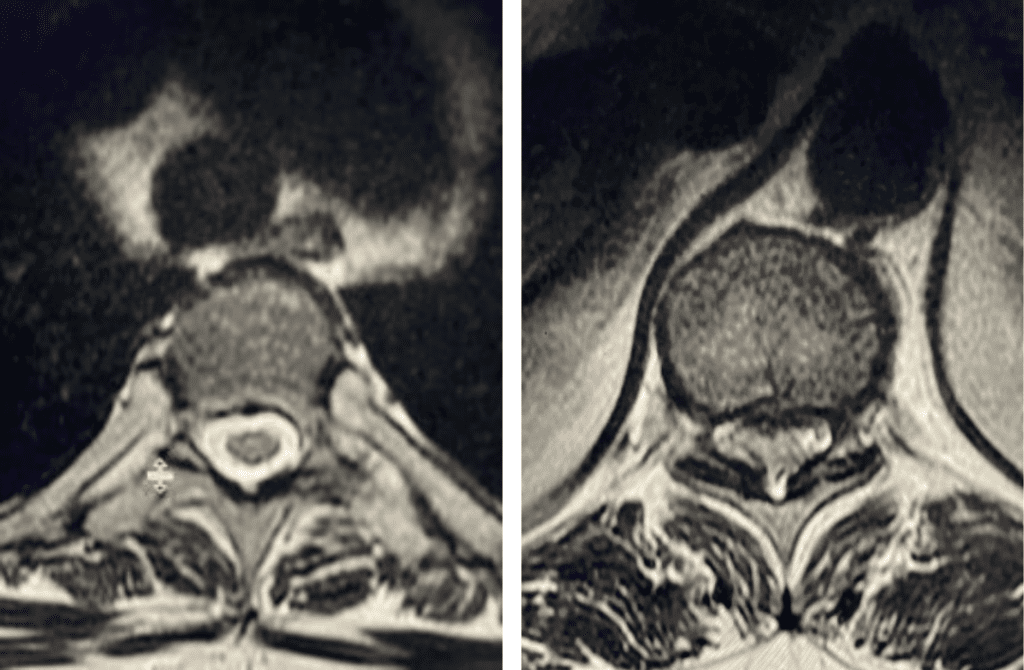

Here is a tough case: This is a 72 year-old male who presented with several months of progressive neck pain without symptoms of the arms or legs. […]